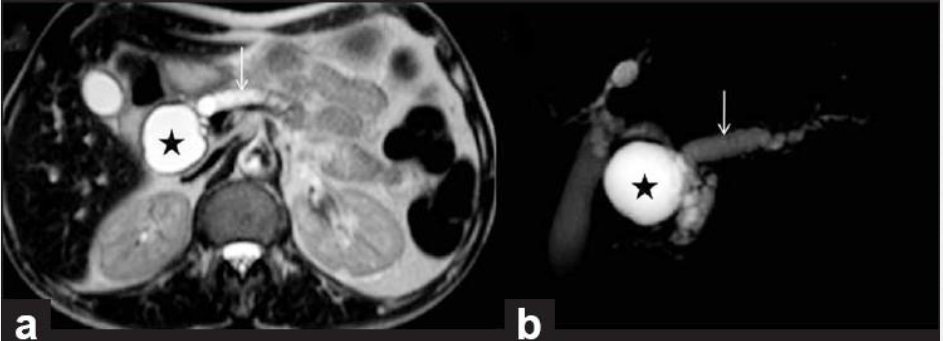

מהו הממצא

פסואודוציסטה בלבלב- דם,אפיתל ושאריות של חלבון שהצטבר

Q

A

הרחבה של צינור הלבלב יחד עם ציסטה, מדובר בציסטה גידולית